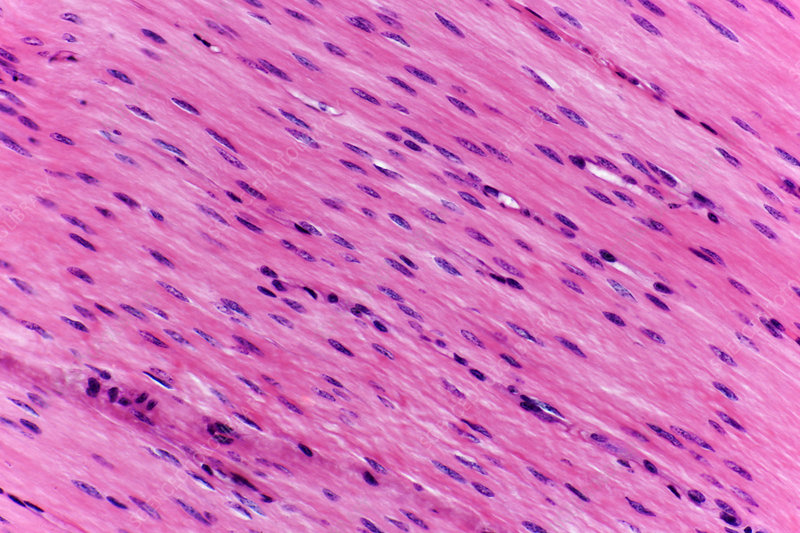

Smooth Muscle

Structure: Spindle-shaped fibers with single nuclei; no striations.

Location: Walls of hollow organs (stomach, intestines, bladder).

Function: Involuntary movements of internal organs.